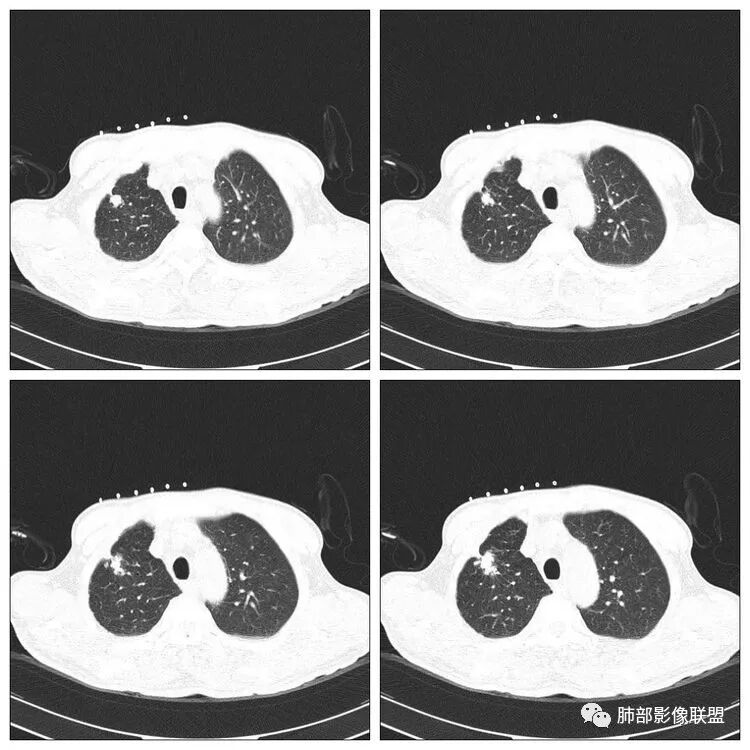

右肺上叶尖段病灶,边缘长、软毛刺,U型征,局部胸膜增厚牵拉,卫星灶。纵隔4R淋巴结增大。

穿越七海的风:右肺上叶病灶,周围卫星灶,U型征,边缘长毛刺,结核首选,恶性肿瘤不能排除。

右侧胸廓稍塌陷,右肺体积稍变小,右肺上叶结节,有膨隆有收缩,局部膨隆明显,见胸膜牵拉,胸膜多发增厚,周围卫星灶,另两肺感觉多发微结节影,应该是有结核的,右肺上叶大结节需警惕合并肺腺癌,建议完善增强和三维重建,另两肺多发微结节,有贲门癌病史,需除外转移瘤。

孙冰伟:老年男性,有贲门癌病史,未提及入院常规检查肺部有问题,右肺上叶尖段病灶,边缘长软毛刺,局部胸膜增厚牵拉,周围有卫星灶。纵隔淋巴结增大,首先考虑良性病变,结核可能性大,建议穿刺活检或CT增强检查。

老年男性,有肿瘤病史,右肺上叶肿块,病灶多发毛刺,胸膜牵拉,边缘考虑月牙铲,病灶见空泡征,病灶体积偏大,有恶性征象我首先考虑肿瘤,鉴别结核。

傅昌瑜:老年男性,有贲门癌史,右上团块影分叶毛刺胸膜凹陷→恶性可能,周围有卫星灶→良性可能。右侧胸廓塌陷,右侧胸膜有较多结节,双侧胸腔少量积液。整体考虑良性可能→结核可能性大。建议增强及穿刺检查。

THINKER:右上肺前段结节,胸膜凹陷征,整体收缩,有空泡征,胸膜多发结节,纵隔淋巴结肿大,双侧胸腔少量积水;考虑恶性,原发腺癌>转移;

前段炎症丶恶性好发,非结核好发部位。

没意见:老年男性,贲门癌病史;CT:右肺上叶前段块状影,病灶由上至下纵轴跨度略长,轴位多个层面提示分叶、膨隆,毛刺,局部平直、内收、凹陷;病灶略散,主体病灶周边卫星灶,支气管树芽征,胸膜增厚,牵拉凹陷,4R淋巴结稍大;整体感觉良恶征象皆有,遗憾没有增强,无法进一步确认,目前转移瘤可能性小,考虑结核可能性较大,需要与原发肺癌鉴别;

老年男性,贲门癌病史。胸CT:右侧胸廓塌陷,右肺体积变小,右肺上叶大结节,深分叶、胸膜牵拉、毛刺,周围卫星灶,两肺多发微结节影,纵隔多发肿大淋巴结,先考虑恶性,结核待排。

小兜:右肺上叶尖段结节,分叶,周边见细长毛刺及胸膜牵拉,周边多发卫星灶,考虑结核可能性大。

老年男性,有贲门癌病史,右肺上叶结节,有分叶毛刺征,胸膜牵拉,周围多发微小结节,纵隔淋巴结肿大,双侧少量胸水,考虑恶性结节可能,结核不排,建议增强。

丽:右肺上叶尖段近胸膜下结节,部分边缘膨隆,可见胸膜牵拉,周围可见多发播散灶,伴双侧胸腔积液,考虑结核可能大,病人有贲门癌病史,老年男性,恶性肿瘤(转移瘤)不除外。

晨:右尖段病灶,边缘长软毛刺,局部胸膜增厚牵拉,周围卫星灶,纵隔淋巴结增大,首选考虑结核可能。

水晶石头:患者老年男性,术前胸部CT发现。胸部CT:右肺上叶不规则结节影,可见分叶、毛刺、胸膜凹陷、平直征象,周边可疑卫星灶。综合考虑良性病灶,结核可能性大,结合其明确诊断贲门癌,鉴别转移及恶性。

老年男性,右肺上叶实性结节,边缘分叶,周围见较多卫星灶微结节,外侧见胸膜牵拉凹陷征,邻近胸膜反应明显。考虑良性病变,炎性肉芽肿可能,结核可能性较大。鉴于患者贲门癌病史,转移待排,建议穿刺。

阿飞:右肺尖段病灶,边缘长软毛刺,局部胸膜增厚牵拉,周围卫星灶,纵隔淋巴结增大,考虑良性,结核可能。

浪迹天涯:老年男性,贲门癌病史,右肺上叶病灶,局部有深分叶,边缘清楚,周围可见多发点状高密度影,邻近胸膜增厚(其脂肪层可见,未被侵犯),1.结核可能性大,2.腺癌合并结核。

良恶性征象都有,部分层面像多个结节堆积,周围见多发点状,小斑片。考虑结核。鉴别原发癌。

🎀丽🍀:右上肺病灶,呈分叶状、毛刺征,临近胸膜凹陷征,周围可见卫星灶。支持结核。

王秀仙:右肺上叶肿块,边缘有平直收缩,部分边缘膨隆,有分叶,有毛刺,周围见较多卫星灶结节,邻近胸膜反应增厚牵拉;考虑结核。

右肺上叶肿块影,边界清晰,其内密度均匀,病灶边缘见分叶,毛刺及胸膜牵拉征,病灶周围见结节及卫星灶,结合病史,考虑腺癌可能,除外转移。

红日东升:老年男性,贲门癌病史。右肺尖段病灶,收缩明显,多发毛刺,胸膜牵拉,局部胸膜增厚牵拉,周围卫星灶,右上叶体积较小。考虑炎性肉芽肿,结核可能,鉴别腺癌。

蔡磊:右肺上叶结节,边缘较清,边缘有收缩,临近胸膜局限性增厚,周围见散在卫星灶,支气管未见明确截断,病灶内密度基本均匀,纵隔内多发增大淋巴结,总体考虑结核,建议增强后再观察,虽然有胃癌病史,转移瘤不是太像。

曹志勇:病灶分叶,局部欠彭隆,胸膜牵拉明显,但周围有卫星灶,首先考虑结核,鉴别腺癌,转移瘤基本不考虑。

马宁强:右肺上叶肿块,边缘有平直收缩,部分边缘膨隆,有分叶,有毛刺,周围见较多卫星灶结节,邻近胸膜反应增厚牵拉;考虑结核。

弹指之间:右上肺结节,毛刺、分叶,局部胸膜增厚牵拉、凹陷,恶性征象比较多,但周围卫星灶,纵隔淋巴结增大,第一考虑结核可能,腺癌待排吧

深分叶、边缘膨隆、胸膜凹陷征及附近多发结节,胸膜不干净,纵隔多发淋巴结

但是呢,我觉得这个病灶,它确实有一些恶性的特点,边缘膨隆,深分叶,有深短毛刺。

感觉胸膜上有很多结节,层面不够,还有一点胸水。

2.右肺上叶斑片影、结节影、硬树丫,密度均匀未见钙化或液化。近胸壁处见分叶结节影及棘状突起,胸膜牵拉凹陷。

4.细看病灶有些散,有堆砌感。注意结核灶也常有胸膜牵拉。